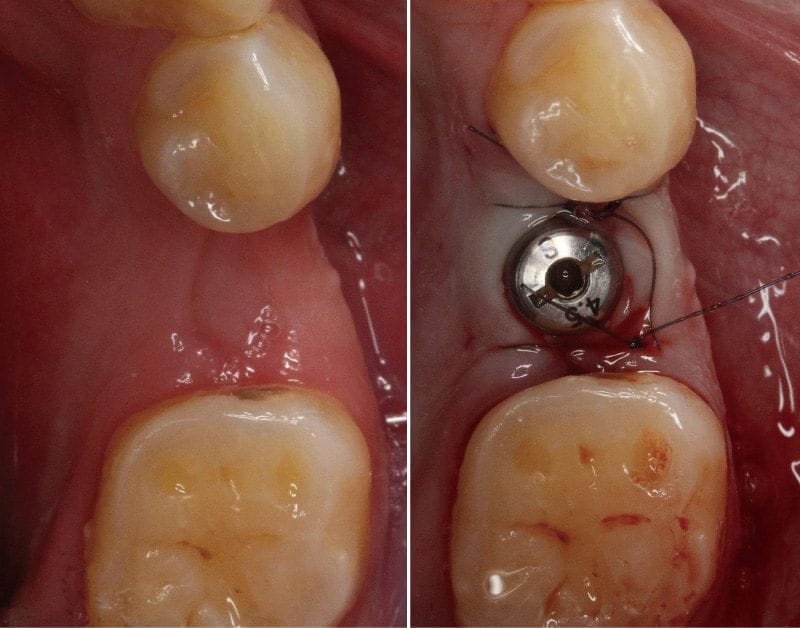

在後牙拔牙之後大約三個月,牙肉和齒槽骨的狀況都已經穩定,再與麻醉專科醫師配合,安排『舒眠植牙』療程。

在植牙手術時利用標靶控制輸液(TCI:Target Controlled Infusion)的方式靜脈注射,這樣可以讓患者在淺眠狀態下接受治療。

舒眠植牙療程必須在術前依照焦慮程度和身體狀況評估,術中配合機器監控血壓、心跳、呼吸、血氧,這樣才能將麻醉的風險降至最低。

通常患者在術後短時間就會恢復清醒,藥物的失憶效果,會讓患者對療程本身不太有印象,對於怕痛的Mr.Su來說,就更能安心放鬆地接受治療。

植牙手術順利且植體穩定度很好,因此以一階段的方式完成,通常這樣大約兩個半月到三個月等待骨整合完成,就可以進入到製作植牙假牙的步驟。

圖示:植牙手術前後示意圖,植入人工牙根,等待骨整合後再進行植牙假牙製作修復